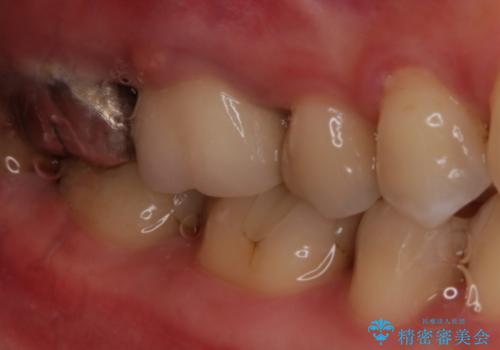

被せ物について

適合不良の補綴物は二次的な虫歯発生のリスクが高まります。

自費診療で用いられる材料は保険適応の材料に比べて、より精密で適合の良い被せ物作ることができるため、長期的な虫歯のリスクを大幅に減らすことが可能です。